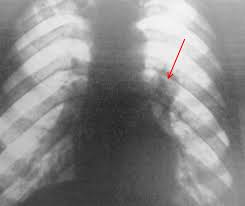

Фиброма легких — очень редкий вид доброкачественной опухоли. Она образуется в бронхах и некоторых элементах легочной ткани. Этому заболеванию подвержены в основном 30―35-ти летние мужчины. При этом вероятность возникновения именно этого вида опухоли составляет всего 7%. Фиброма захватывает оба легких и начинается с разрастания на внешней стороне органа. Новообразование долго растет и лишь через 3 года заставляет больного прийти к врачу. Из-за скудной симптоматики и несвоевременного обращения за помощью процессы в легочных тканях приобретают необратимый характер.

Обычно фиброматоз легкого имеет периферическую локализацию, при котором опухоль крепится к легкому с помощью узкой ножки. Размер данного образования зачастую около 2―3-х сантиметров, но известны случаи разрастания опухоли до гигантских размеров, вплоть до половины грудной полости. Фиброма легких является доброкачественной болезнью, поэтому вероятность перерождения опухоли не существенна. Образование имеет форму однородной эластичной капсулы, которая не контактирует со здоровыми тканями. Внутри фибромы иногда формируется костная ткань.

В начале заболевания фиброма практически никак себя не проявляет. Хоть иногда присутствует мокрый кашель, с помощью рентгена обнаружить ее не получается. Первыми признаками становятся повышение температуры, кровохарканье, боль в груди, хроническая усталость, одышка. На рентгенологическом исследовании уже визуализируется процесс воспаления. Для следующей стадии характерно удушье, повышенное потоотделение, лихорадка, внешняя деформация грудной клетки, легочные кровотечения и грудные боли.